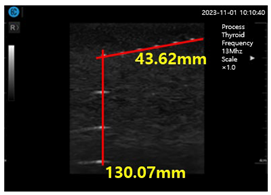

Figure 15a shows ultrasonic gel testing at various time intervals using the ATS-539 phantom. Figure 15b shows the sharpness of the image of the manufactured gelatin soft gel after storing it in alcohol and performing a sharpness test at 1 h intervals for 72 h. The results are presented in Figure 15b. In this paper, the experiment using a soft solid gel did not require IRB agreement. This research on the proposed gelatin soft solid gel showed its functionality to be better than that of ultrasonic gel, including on grayscale, echo, and color. This means that it can overcome the tissue density dead zone to increase high resolution performance. To help imaging accuracy, it is proven that gelatin soft gel, especially the soft solid gel, can replace ultrasonic gel to simplify disinfection and ensure permanent use. Image corrosion testing of gelatin soft solid gel for 30 min is shown in Figure 16a. Ultrasonic gels were tested at different times using an ATS-539 phantom, where the gel was soaked in ethanol for 72 h, as shown in Figure 16b. Afterwards, the gel’s condition was tested again. Finally, Figure 16c measures the imaging resolution of the gelatin soft tissue gel.